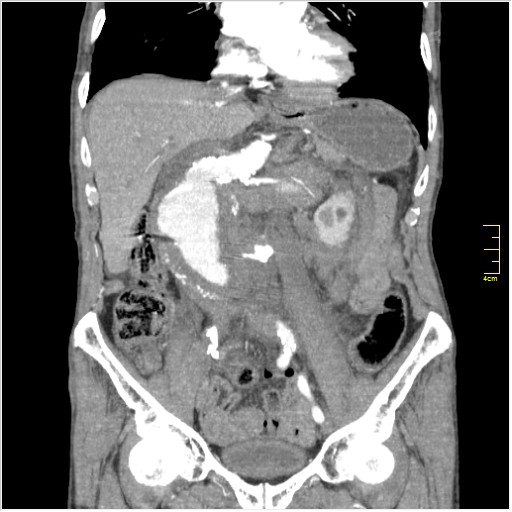

КТ брюшной полости. Мужчина с пальпируемой опухолью в животе

Пациент Т. 64 года, обратился на КТ брюшной полости амбулаторно (!), по направлению семейного врача с диагнозом abdominal mass, буквально: образование брюшной полости.

Huge abdominal aorta aneurism. Simple renal cortical cysts (Bosniak type 1).